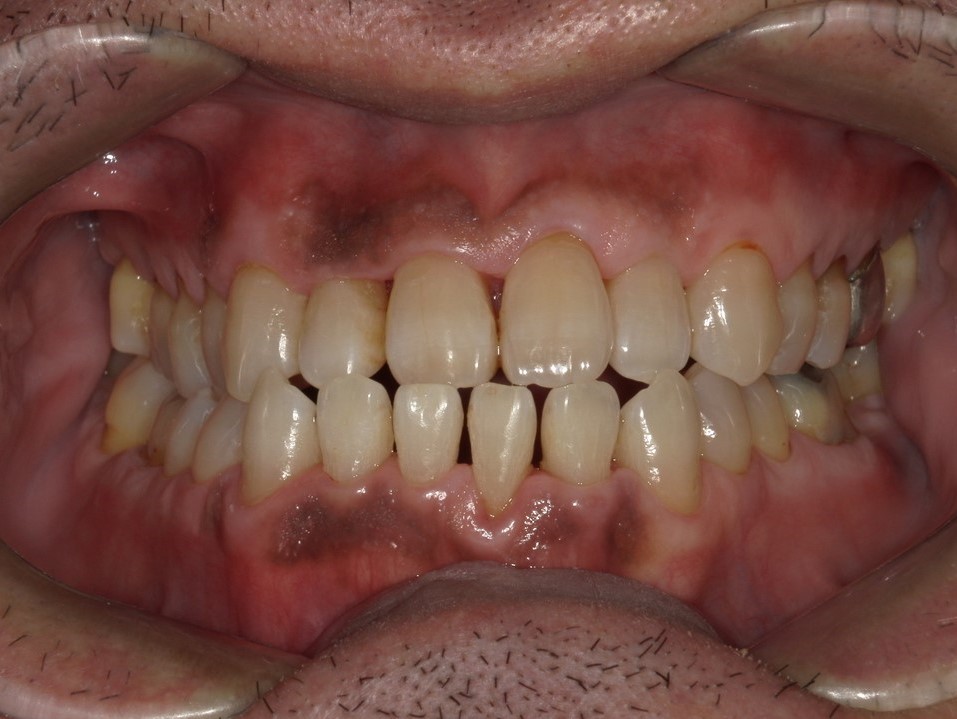

そしてこちらが何回かクリーニングをした後の状態です。

明らかに歯茎の色や形がきれいになっているのがわかります。これをご本人に見てもらい、初診時と比べてもらうとその変化に驚きと喜びがあふれていました。

こういった視覚的な変化を確認できると患者さんはモチベーションが上がるんです。この方は以前と比べて口腔内への関心が高まり、その後、定期的にメンテナンスで通っていただくこととなりました。